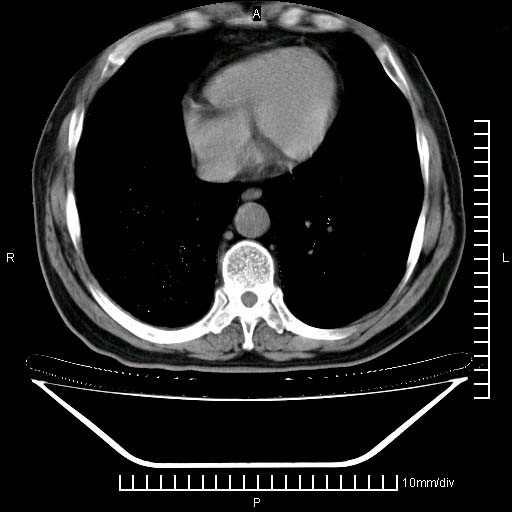

标题: CT24043:胸部增强:男性,60岁 [打印本页]

标题: CT24043:胸部增强:男性,60岁

既往肺结核,近10几天,咳嗽,咳痰,右侧胸痛,疼痛较明显,右上肺斑块考虑结核灶胸膜粘连,增强,可惜动脉期没有定好,未见强化,可延迟4分后又见较明显强化,中心见低密度影,如果说结核是边缘强化,可这个灶强化的面积挺大的,让人很挠头。

动脉期